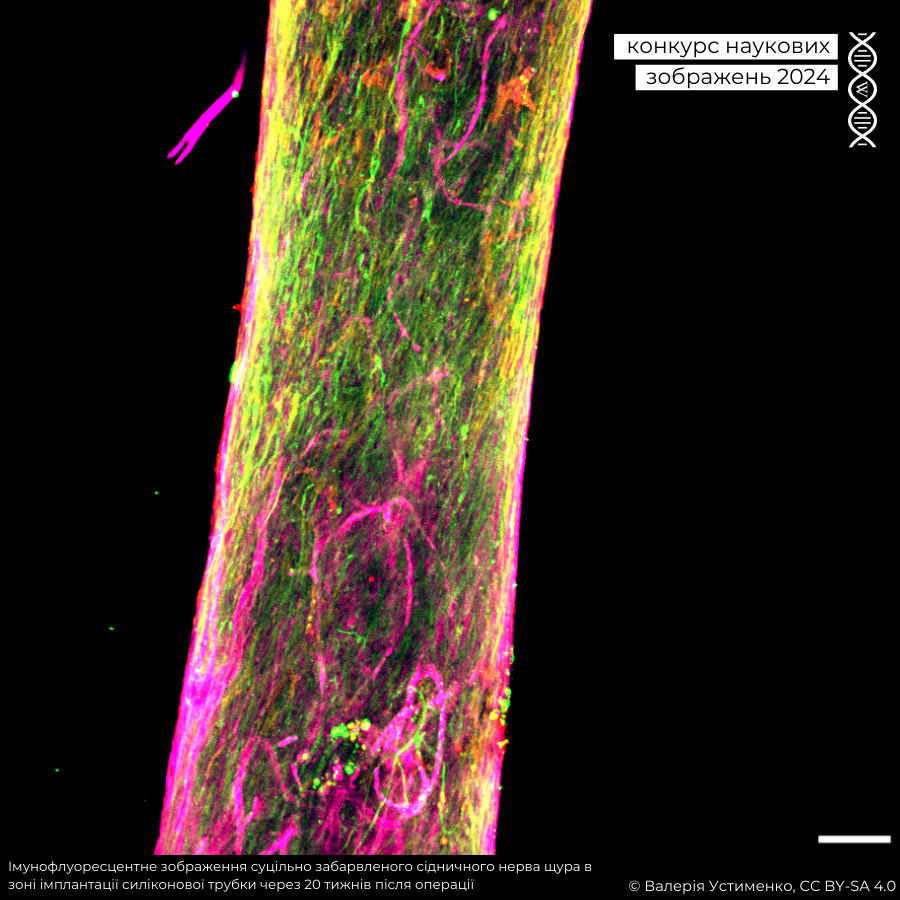

«Мені дуже сподобались різноманітні наукові перспективи, представлені в цьогорічному конкурсі, особливо захоплива робота в галузі тканинної інженерії та імплантів, яка має надзвичайну актуальність у воєнний час.

На другому місці імунофлуоресцентне зображення суцільно забарвленого сідничного нерва щура в зоні імплантації силіконової трубки через 20 тижнів після операції отримане методом конфокальної мікроскопії. Авторка — Валерія Устименко.